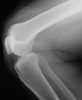

You order frontal, lateral, and sunrise radiographs of the right knee. What do these films reveal about the extent of this patient’s injury?

Knee pain following a soccer injury: The frontal radiograph reveals that the patella is dislocated laterally (A). This is confirmed on the sunrise radiograph (B). A lateral radiograph shows the malalignment of the patella with the distal femur (C). Most important, it also shows no fracture. Lateral dislocation of the patella is diagnosed.